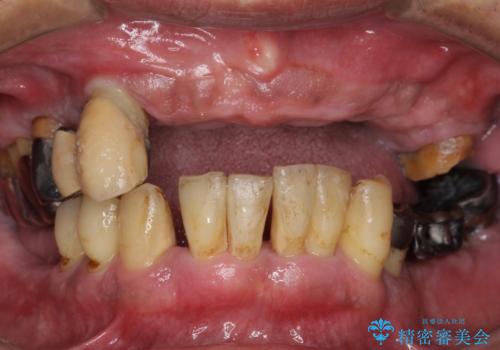

- 歯がぐらぐらで咬めないことを主訴に来院された患者様です。

仕事が忙しくなかなか自分のことに気が回らなかったそうですが、どんどん歯の動揺が増し「もう限界だ!」と思い受診を決断したとのことでした。

精査したところ、全顎的な重度の歯周病により下顎前歯に激しい動揺を認めました。

骨吸収と動揺が著しい前歯1本(左下1)のみ抜歯しております。